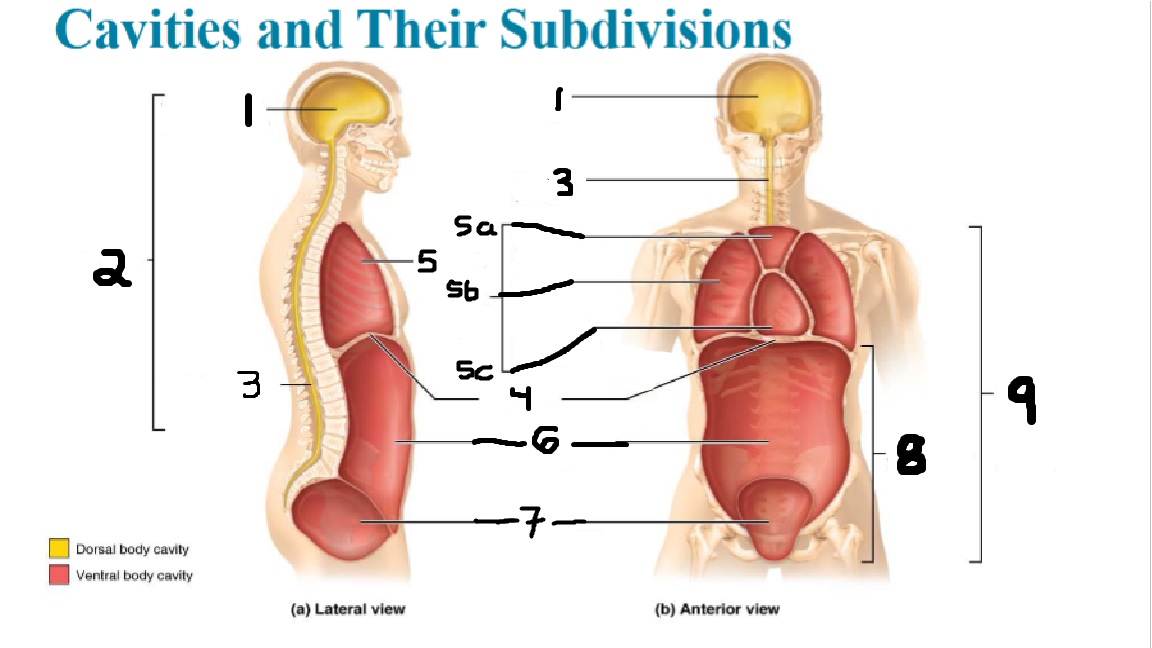

What cavities are part of the dorsal cavity?

The cranial and the Spinal (vertebral) cavities

What kind of cavity is labeled 2?

The dorsal body cavity (containing the cranial and spinal cavities)

What is the purpose of the dorsal cavity?

protects the nervous system

What is the main organ encased by the cranial cavity?

the brain

What cavity is labeled #1?

The cranial cavity

What is the main organ encased by the vertebral cavity?

the spinal cord

What is another word for the vertebral cavity?

the spinal cavity, or the spinal canal

What body cavity is labeled 3?

the vertebral cavity.

What cavities are included in the ventral cavity?

the thoracic, abdominal, and pelvic cavities.

What body cavity is labeled #6?

the abdominal cavity.

What are the main organs of the abdominal cavity?

the digestive organs such as the stomach, intestines, spleen and liver

What cavities are included in the Abdominopelvic cavity?

the abdominal cavity and the pelvic cavity

What body cavity is labeled #8?

The Abdominopelvic cavity

What does the diaphragm separate?

the thoracic and the abdominal cavities

What is labeled #4?

the diaphragm

What organs does the pelvic body cavity contain?

urinary/reproductive organs and rectum

What is labeled #7?

the pelvic cavity

What does the thoracic cavity encase?

the heart and the lungs

What is labeled #5?

the thoracic cavity

What part of the thoracic body cavity is labeled 5a?

superior mediastinum

What part of the thoracic body cavity is labeled 5b?

pleural cavity

What part of the thoracic body cavity is labeled 5c?

pericardial cavity within the mediastinum

What body cavity encloses the heart?

the pericardial cavity.